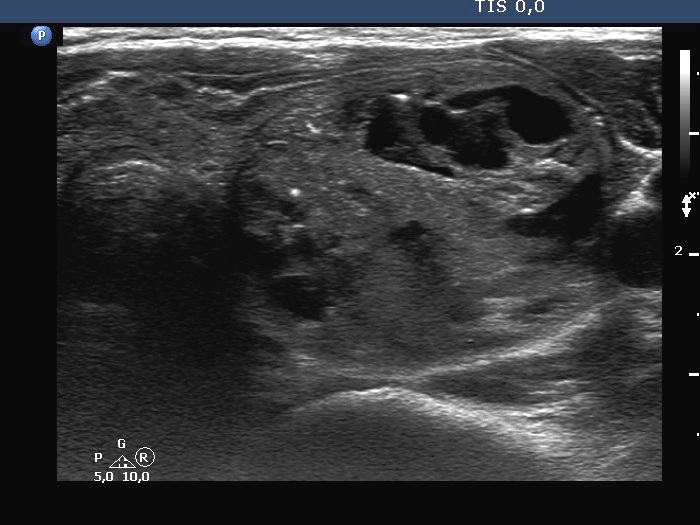

Ultrasonography. The thyroid was minimally-moderately hypoechogenic. There was a large solid-cystic nodule in the left lobe. The nodule belonged to multi-chambered, central subgroup. The nodule did not increase in size in the last ten years.

Comment. The proportion of cystic areas is less than 50%, therefore this nodule should be held as a solid one which has cystic areas.